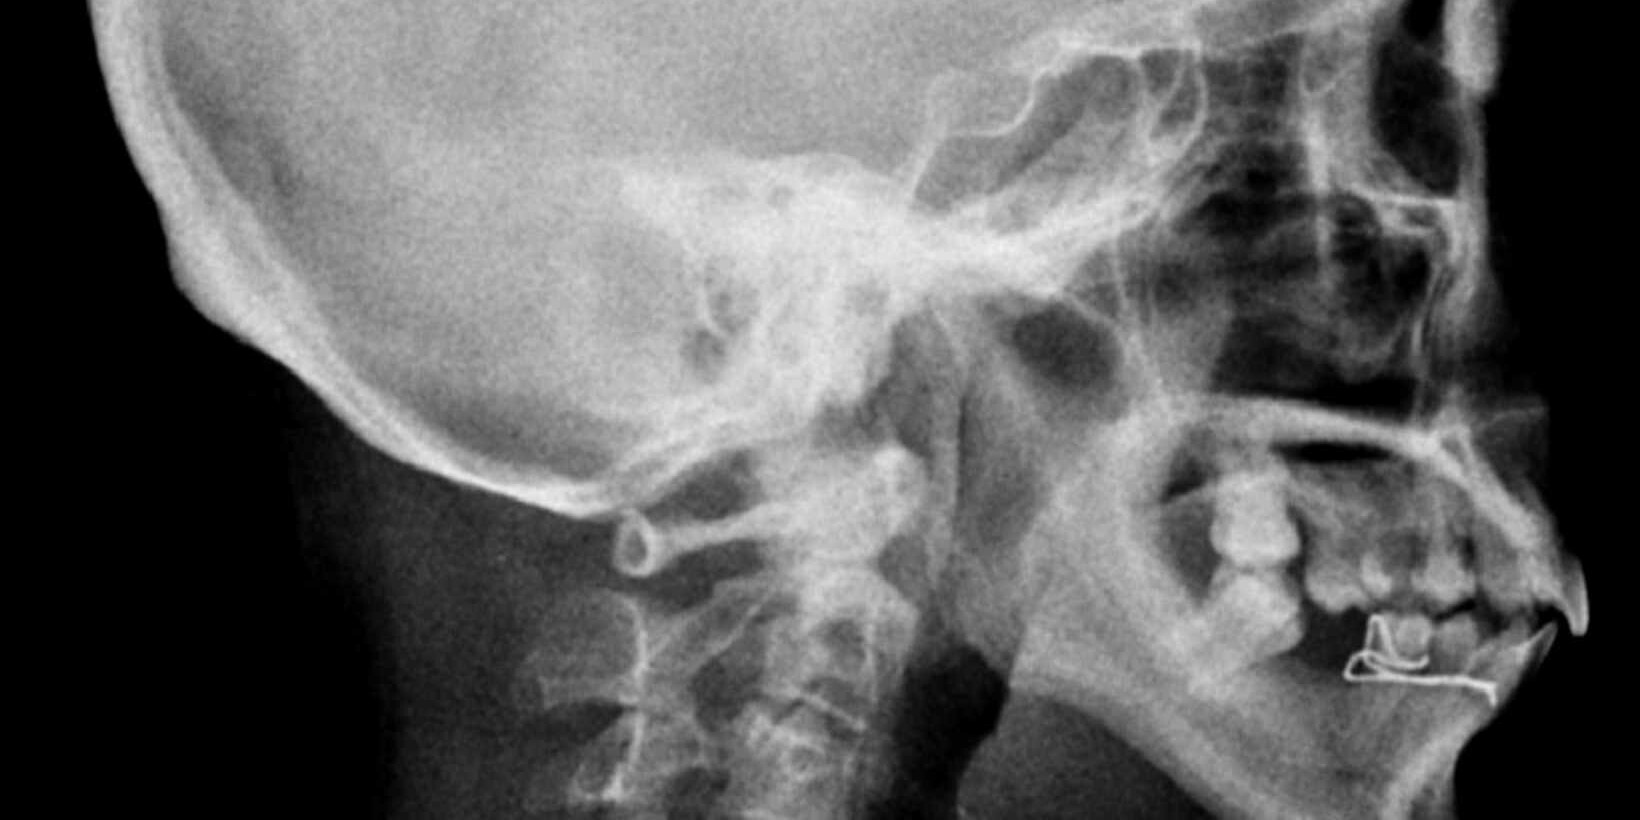

Arnold Chiari Malformation Radiology Insights

Arnold Chiari Malformation (CM) is a condition where brain tissue extends into the spinal canal,…